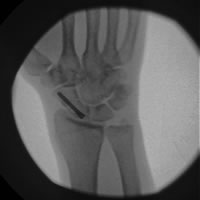

- Simple, minimally displaced fractures may be better managed with a small operation through a 1cm incision on the back of the wrist to place a screw across the fracture and compress the fragments together. The advantage of this is that patients spend less time in plaster and the rate of fracture healing is slightly higher.

- Complex, displaced fractures require open surgery to realign the fragments and stabilize them with a screw. This is done through an incision on either the back or front of the hand/ wrist.

- Non-unions are complex to treat and if left, there is a high risk of developing wrist arthritis (Link to writ arthritis page). Following investigation, patients require an open operation to realign the fracture fragments. At the same time Mr. Hacker will take a bone graft from the pelvis (the boney bit where your belt sits) and place this in the gap formed by the non-union. The scaphoid and bone graft are then compressed with a special screw. This process helps to stimulate the fracture to heal.